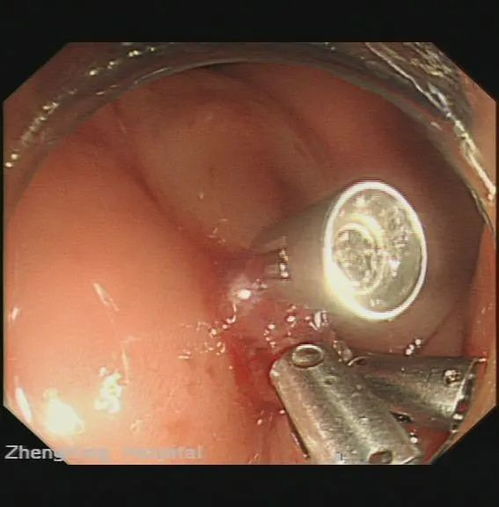

APUD瘤:APUD系统细胞发生的肿瘤,如嗜铬细胞瘤、甲状腺髓样癌、胰岛细胞瘤等。

针对APUD系统相关的疾病,诊断和治疗措施主要包括以下几方面:

诊断:通过实验室检查、影像学检查、病理学检查等方法,对APUD系统相关的疾病进行诊断。

治疗:根据疾病类型和严重程度,采取相应的治疗方法,如手术治疗、药物治疗、放疗等。